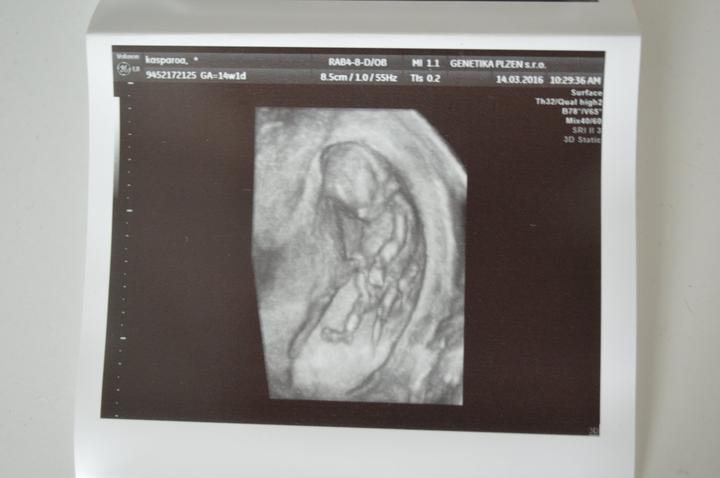

Zítra konečně na screening 🙂 těším se až přítel uvidí toho našeho drobečka 🙂 a že bude vše v pořádku 🙂 byl jste někdo v plzni v Černicich? 🙂 jak jste byli spokojeni? 🙂